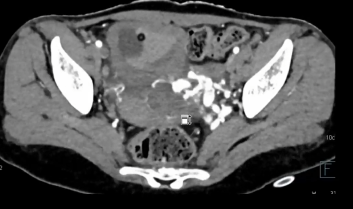

18岁女性,首次出现突发性肉眼血尿和失血性休克。急诊室复苏治疗后生命体征平稳。初步超声显示显示膀胱扩张伴血块、大的弥漫性盆腔AVM及双侧输尿管积水。开始膀胱冲洗以清除血块,MRI及CTA显示盆腔动静脉畸形。由于再次出现大出血,转介入放射科行血管栓塞术

病例二 37岁男性,下腹部疼痛,恶心呕吐三天,无疾病史 增强腹盆部门血管造影计算机断层扫描显示左侧骨盆动脉窝位于左侧骨盆旁空间,伴有肿大、部分形成血栓的骨盆引流静脉以及由输尿管压迫和膀胱移位导致的双侧积水。 | ||||||||||||||||||||